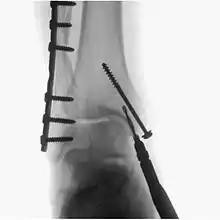

A fluoroscopy X-ray machine is a great asset during surgery for implants

Fluoroscopy is used in various types of surgical procedure, such as orthopaedic surgery and podiatric surgery. In both of those, it is used to guide fracture reduction and in use in certain procedures that have extensive hardware.[5]